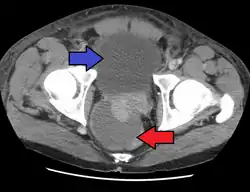

People who are severely ill may need hospitalization, while others can be treated at home with bed rest, analgesics, stool softeners, and hydration. Men with acute prostatitis complicated by urinary retention are best managed with a suprapubic catheter or intermittent catheterization. Lack of response to antibiotics should raise the suspicion of an prostate abscess and prompt an imaging study such as a transrectal ultrasound (TRUS).[10]